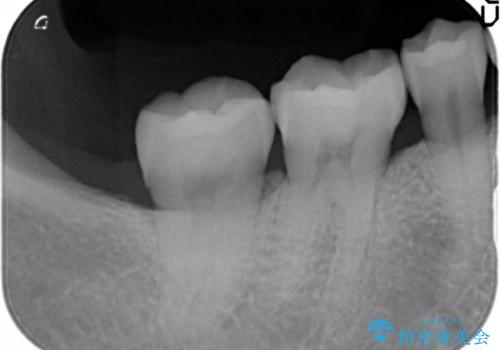

銀歯を白く セラミックインレーに

- 銀歯にしたのが20年以上前とのことで、白くやりかえたいということでした。

セラミックインレーにしています。

- 7万円(左下6 emaxプレスインレー 7万円)費用は治療当時の料金となります

銀歯を外して、下に虫歯があればしっかり取ります。しみるなどの症状が出る前がおすすめです。